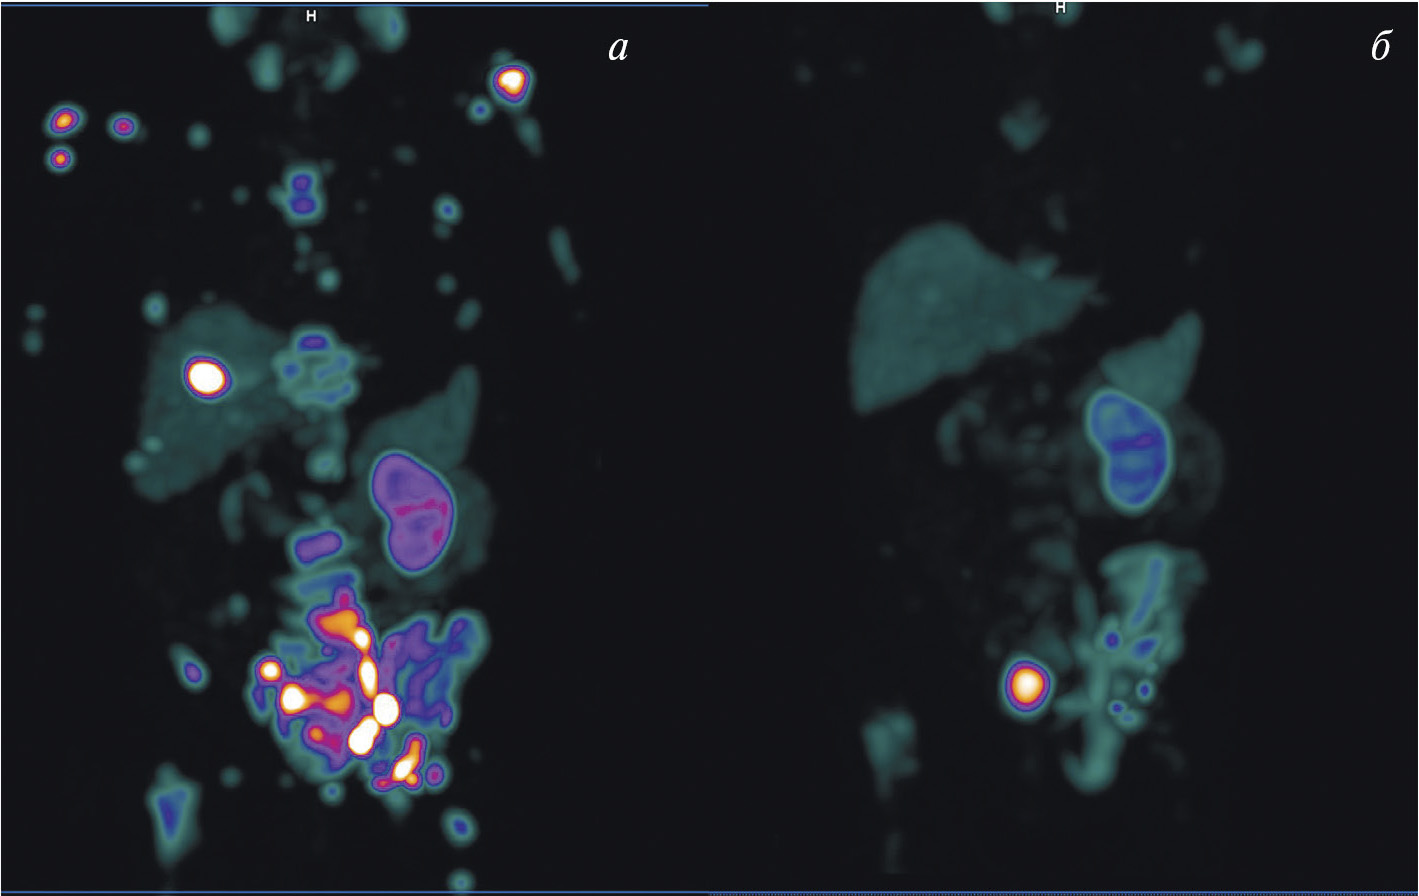

К настоящему времени создан ряд специфичных для GRPR радиоактивных индикаторов, которые подразделяются на агонистов и антагонистов гастрин-высвобождающих рецепторов. Считается, что антагонисты весьма перспективны в качестве основы для разработки радиофармацевтических лекарственных препаратов. Их преимущество заключается в отсутствии побочных эффектов, характерных для агонистов и обусловленных запуском клеточных сигнальных путей. Более того, плотность сайтов связывания антагонистов выше, чем у агонистов, что приводит к лучшему соотношению накопления препарата в опухоли и нормальной ткани. На базе антагониста GRPR разработан 99mТс-RM26 для ОФЭКТ/КТ-диагностики рака простаты и молочной железы. Клинические испытания этого препарата, выполненные в НИИ онкологии Томского НИМЦ, подтвердили возможность его применения для визуализации этих типов рака (рис. 5) [31, 32].

Рис. 5. ОФЭКТ/КТ с 99mТс-RM26 пациентов с раком простаты (а) и раком молочной железы (б) Стрелками обозначено накопление РФЛП в опухоли и лимфогенном метастазе

Изотопы таллия (201Tl и 199Tl) выступают биологическими аналогами К+, проникают внутрь клетки с помощью Na-K-ATФ-зависимой помпы и локализуются преимущественно в митохондриях. Эти радиофармпрепараты активно аккумулируются в тканях с интенсивным энергетическим обменом (к числу которых можно смело отнести злокачественные клетки) и способны участвовать в диагностике самых разнообразных опухолей, включая рак молочной железы, гортани и гортаноглотки (рис. 6) [38]. Кроме того, нуклиды таллия могут использоваться для динамической оценки противоопухолевой терапии [39]. Разработанный в ТПУ и Томском НИМЦ 199Tl выгодно отличается от своего известного аналога 201Tl коротким периодом полураспада (7.4 и 72 ч соответственно) и более низкой дозовой нагрузкой в процессе диагностической процедуры.

Рис. 6. ОФЭКТ с 199Тl пациента с раком молочной железы Стрелками обозначено накопление РФЛП в опухоли